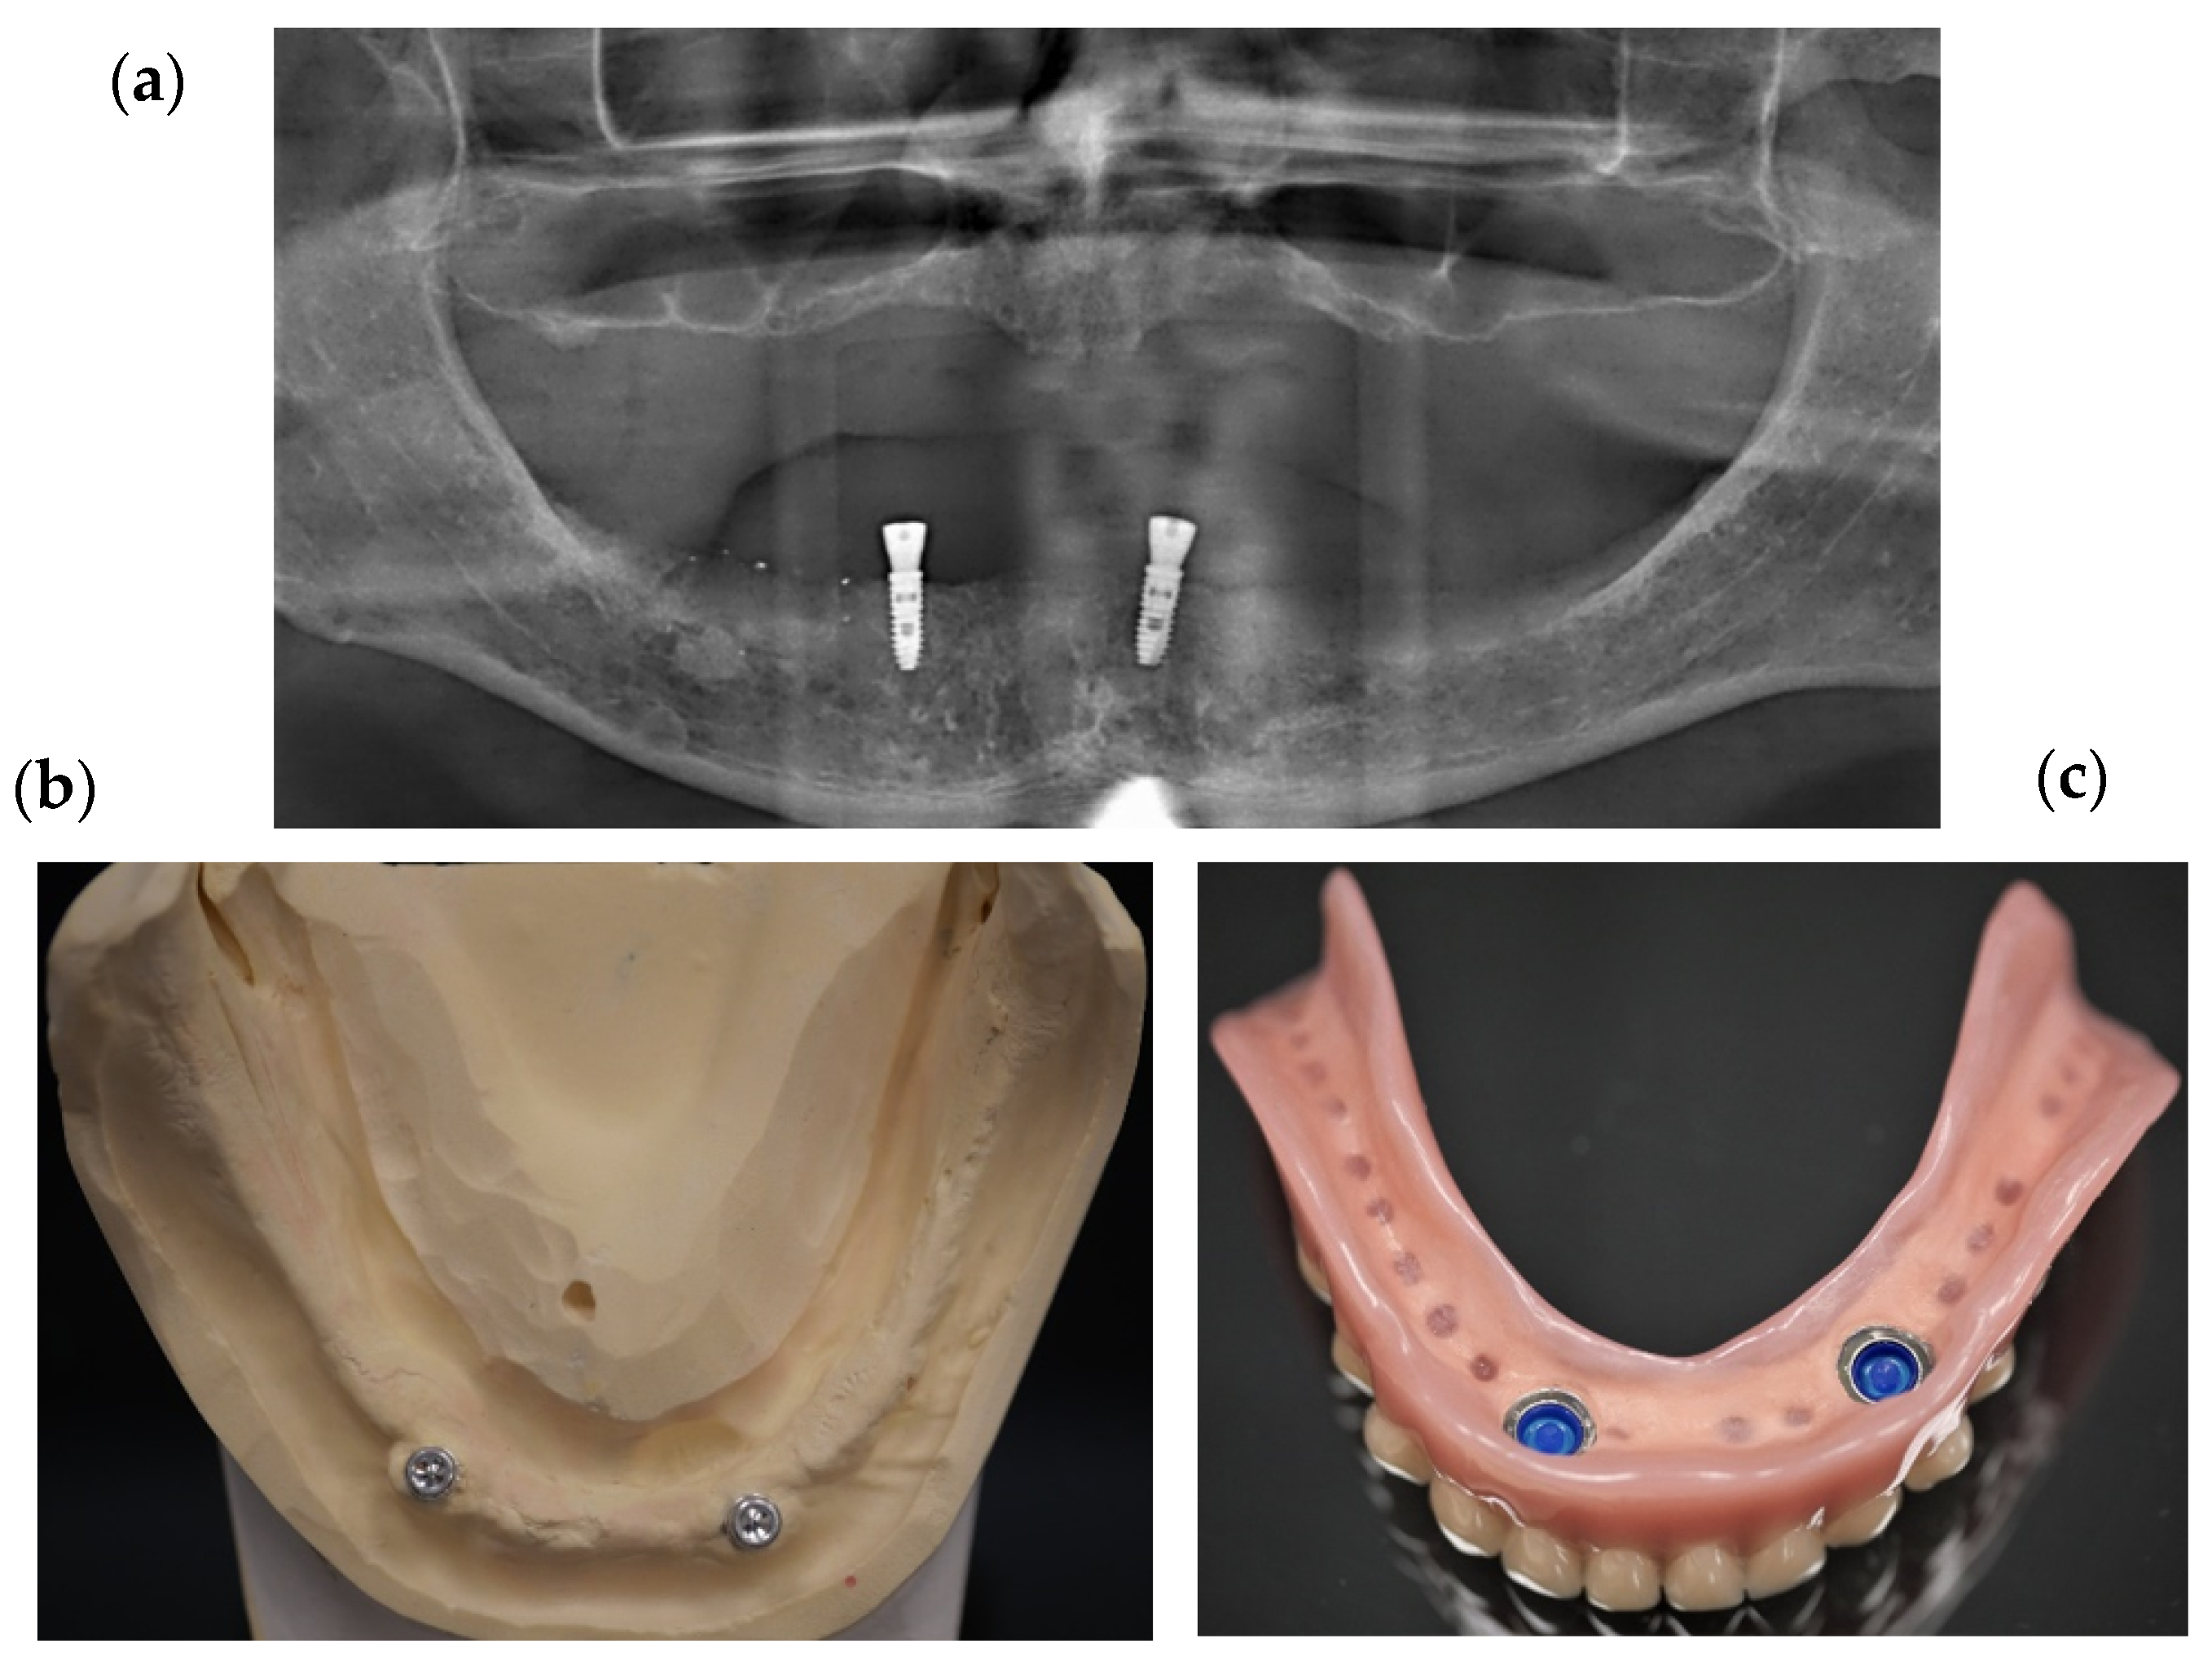

2. Materials and Methods

2.1. Design and Prototype Manufacturing